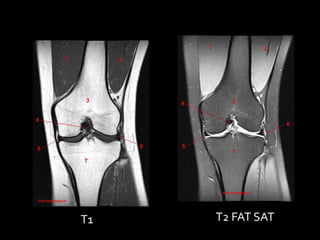

T1   T2

T1   T2 FAT SAT